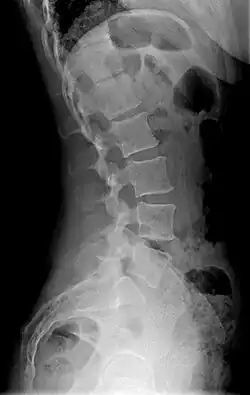

La lordosis es una curvatura de la columna vertebral en la región cervical de convexidad anterior (o concavidad posterior). Se puede presentar tanto de forma fisiológica como de forma patológica.[1] Una lordosis se forma mediante la diferencia de altura de la porción anterior de los discos vertebrales involucrados con respecto a la porción posterior. Esta diferencia provoca una mayor presión sobre las partes posteriores de los discos vertebrales y los desplaza hasta posiciones anteriores.[1]

La lordosis fisiológica es un tipo de curvatura fisiológica de convexidad anterior o concavidad posterior, ambas denominaciones son equivalentes. Existen en el cuerpo humano 2 lordosis fisiológicas: cervical, ubicada entre C2 y T1, y lumbar, entre L1 y L5. Estas se pueden observar en la posición de bipedestación desde una vista lateral.[1]